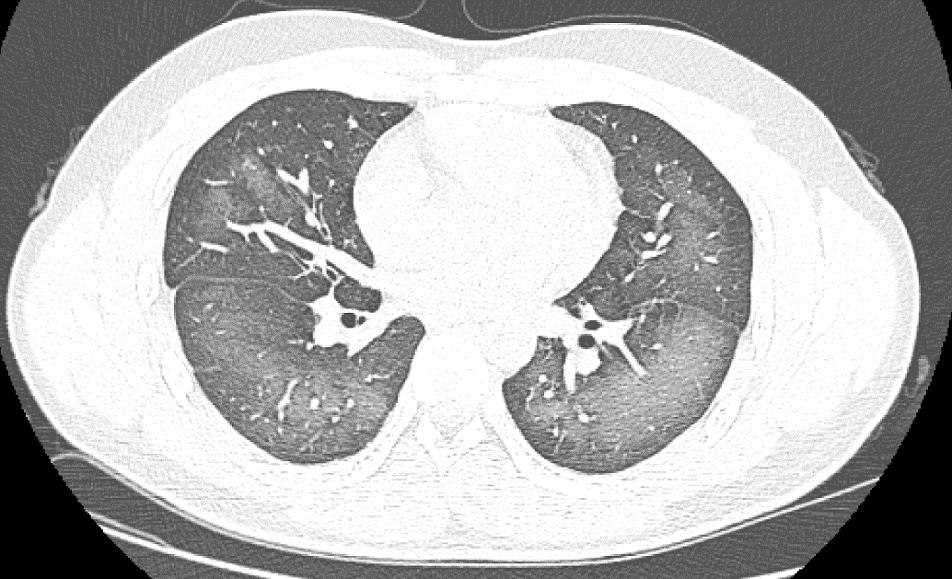

经检查,肺部 CT 片显示,李林双肺赫然呈现大范围白色样病变,报告提示 " 白肺 "。

长沙市第三医院放射影像科副主任、主任医师肖海清表示," 白肺 " 一般是指重症肺炎在 X 线或 CT 检查下的表现,患者肺部呈现一大片的白色状态。" 白肺 " 患者往往会出现呼吸困难、呼吸衰竭,严重者还会出现其它脏器功能障碍。" 白肺 " 常见于高龄(65 岁以上)、免疫力低下、有重要器官慢性病史(如心脏病、中风史、慢性肾脏病、慢性阻塞性肺疾病等)、有多种疾病并存(比如既有高血压、糖尿病,又有心脏病、肺病、肾功能不全)等人群。

长沙市第三医院放射影像科主任张秀萍表示,除了感染、弥漫性肺泡出血综合征等 " 白肺 " 最常见的病因外,吸入有害物质如粉尘、喷雾等,也可导致肺部出现大范围白色样病变。这位年轻的患者就是因为使用不当,吸入了一部分防晒产品进入肺部,导致 " 白肺 " 的发生。